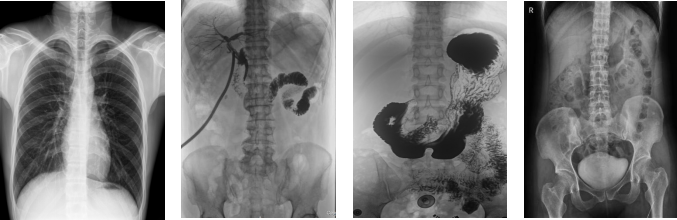

PLD8000C數(shù)字胃腸DR機全面突破傳統(tǒng)X射線攝影透視理念,成像部件采用新型動態(tài)平板探測器,輕松解決數(shù)字攝影、數(shù)字透視、數(shù)字造影等功能,并使數(shù)字透視獲得超大尺寸和清晰的圖像效果。滿足放射科、體檢中心、影像中心、內(nèi)科、婦科、外科、急診科、骨科、創(chuàng)傷科、消化科等科室的各種臨床檢查需求。如果您想采購這款數(shù)字胃腸DR機,歡迎咨詢400-025-6366。